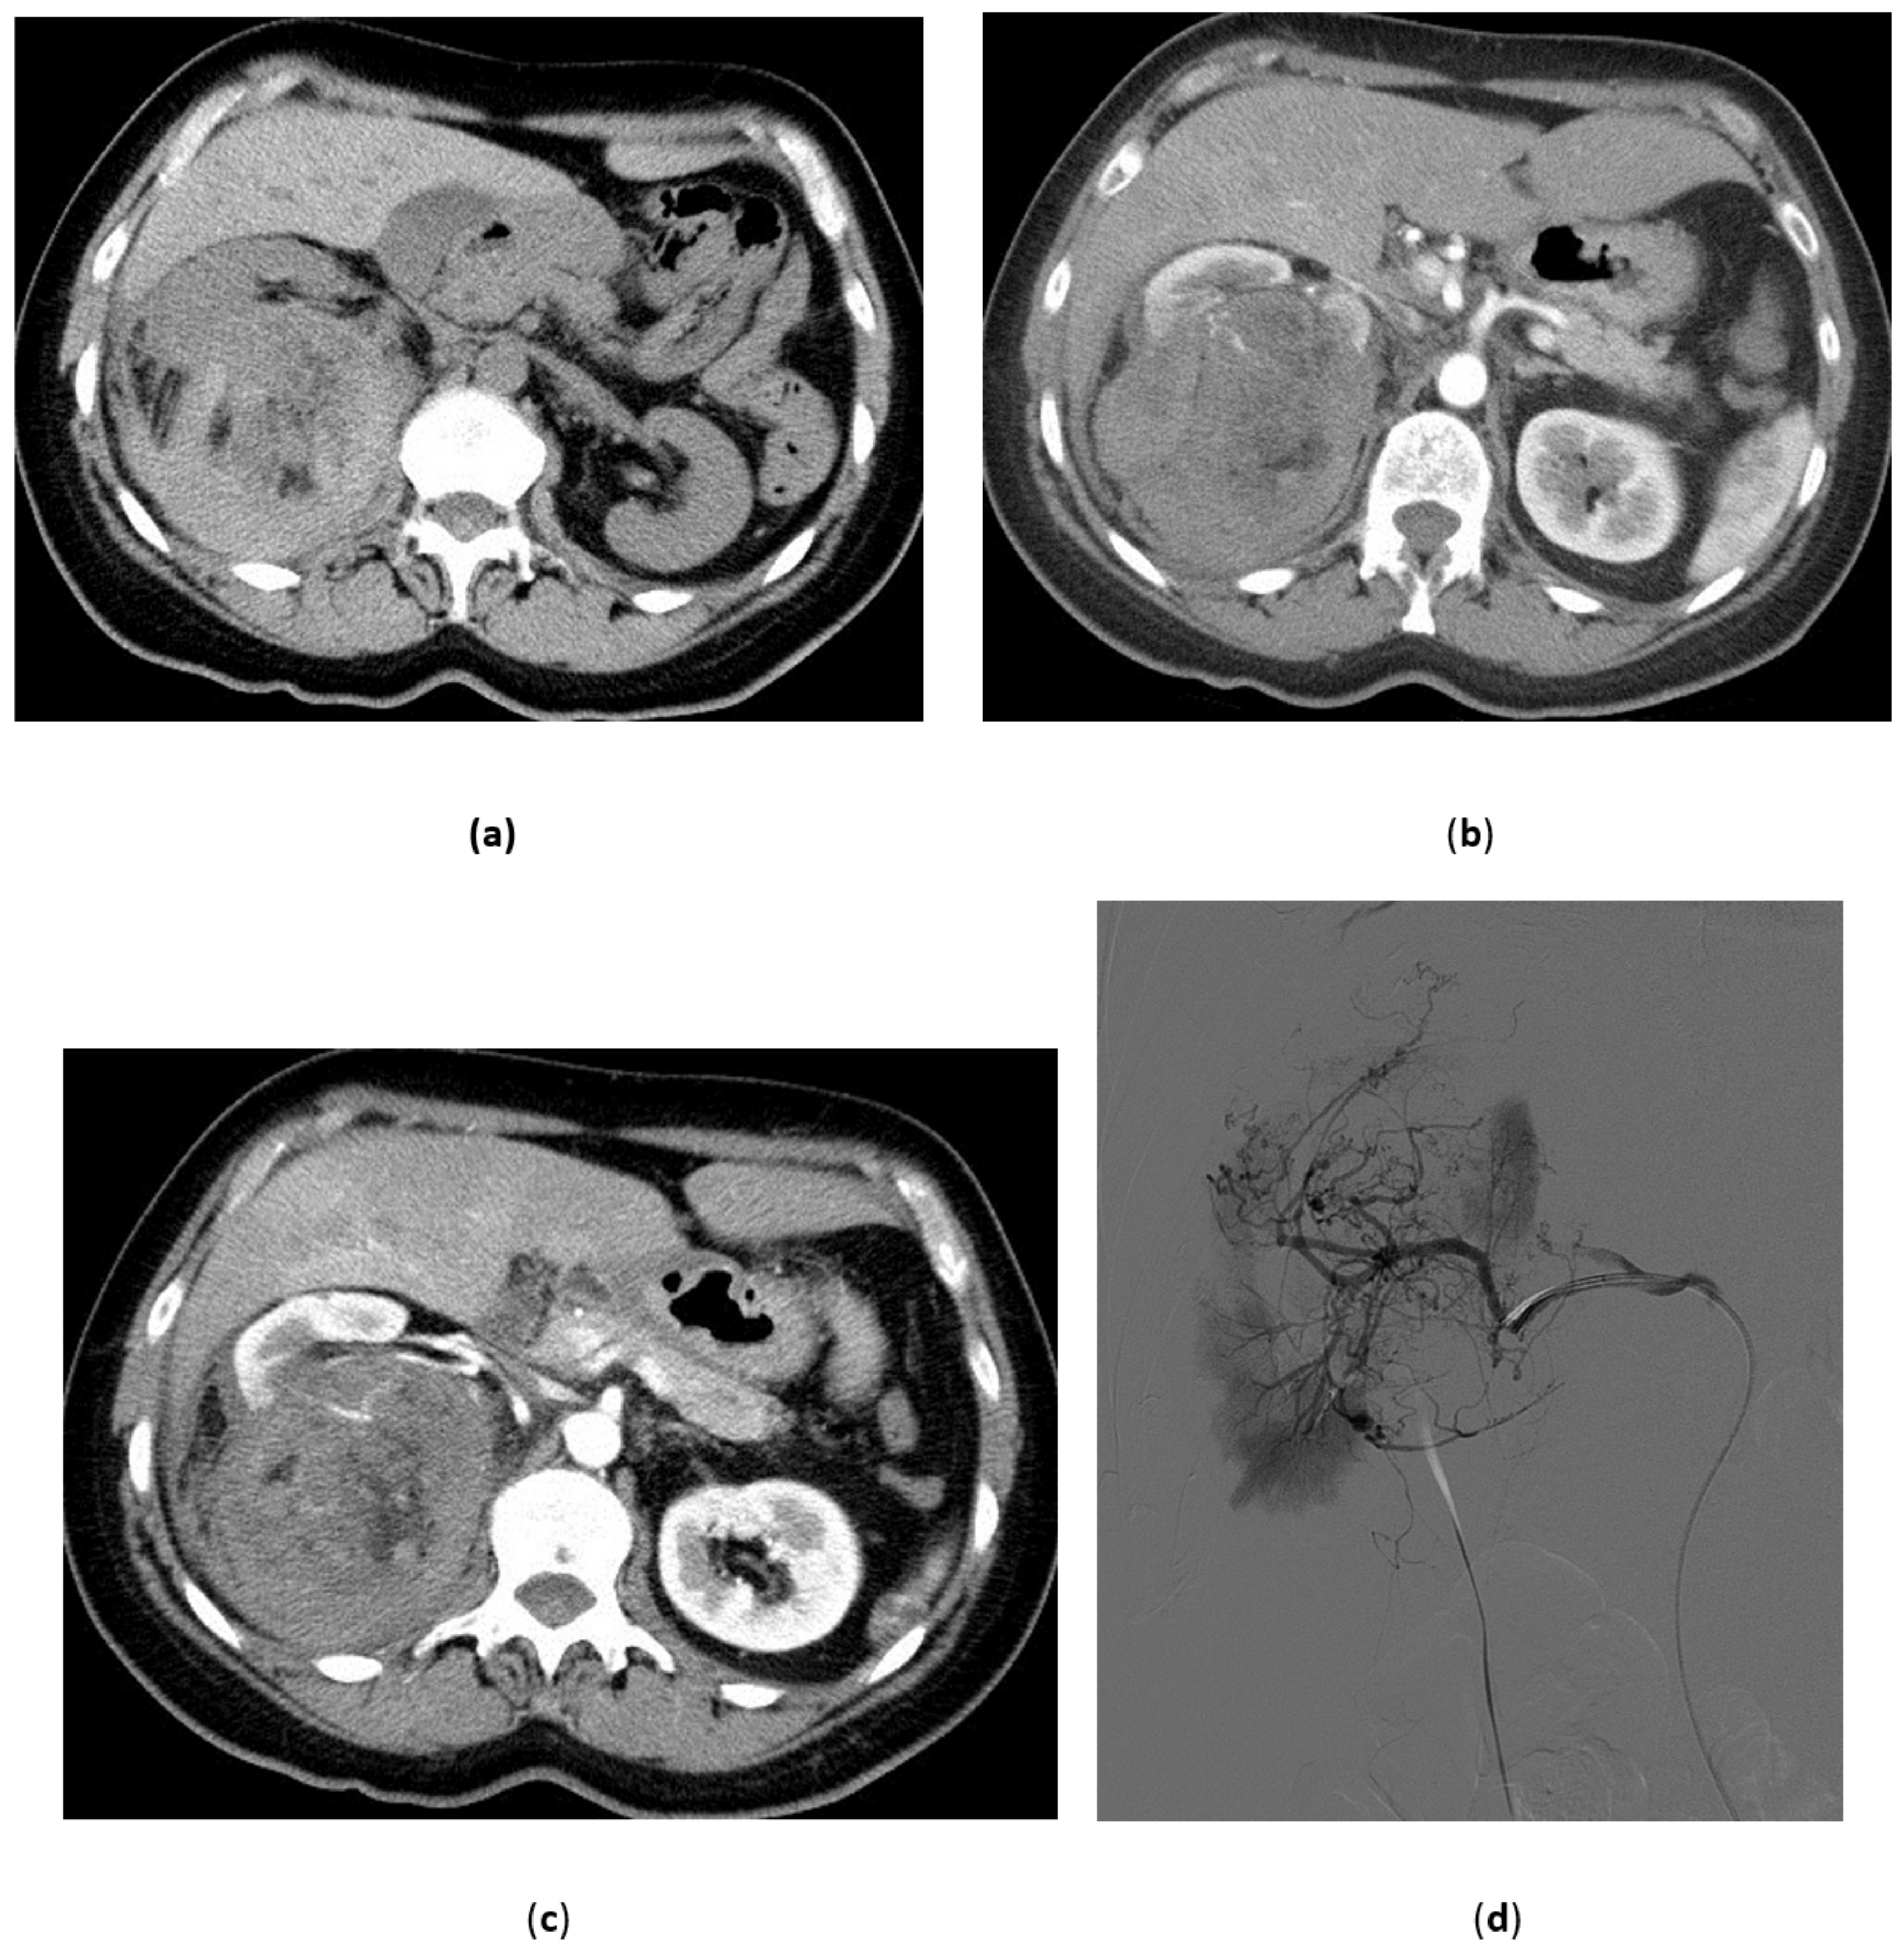

3.5. Renal Angiomyolipoma

3.6. Malignant Renal Tumors